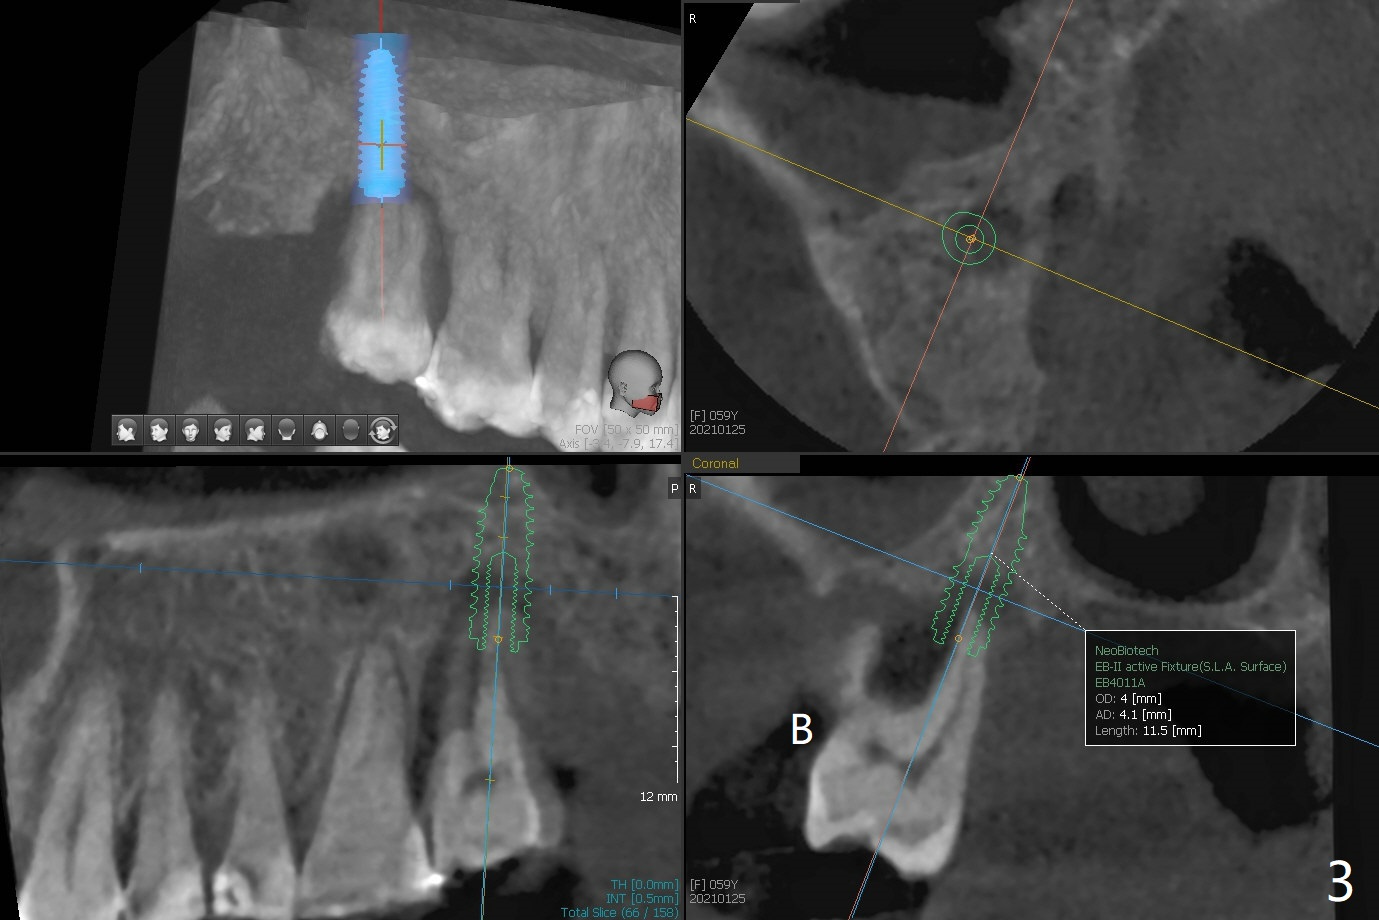

59岁女两年前就诊,主诉右上7,8之间食物坎塞,没有注意7骨质吸收(图一),以为是8过度延申所致拔除,而且远中颊侧,腭侧根断裂(间接说明咬合力大),前者拔除,而后者滞留。如果不拔除,现在支撑导板多好。两年后病人认为断根长出来,其实腭侧根尖仍在骨中(图二(半年前拍摄):箭头),而7骨质吸收更严重,松动2度,怀疑根裂(咬合力大)。同时病人可能有骨质疏松,拔除即刻种植,基台一定要短,一旦牙槽窝愈合,考虑取出临时牙冠,减少微动。取模前,进行渐进性负荷。术前服用Z Pack,准备上颌窦提升,PRFx2。CT显示上颌窦提升不需要,植体可以植入腭侧窝(图三)。 CT冠状切面(图四),矢状切面(图五)显示必须使用长袖的基台(粉红色)固定粘性骨粉(红色),这样植体(绿色)稍微可以种得浅些。箭头:cotton roll(颊侧牙龈沟)。为了让病人在制作导板时舒服些,利用邻牙做冠外固定7松动牙(III)。7颊侧软组织缺失(图六:*)。